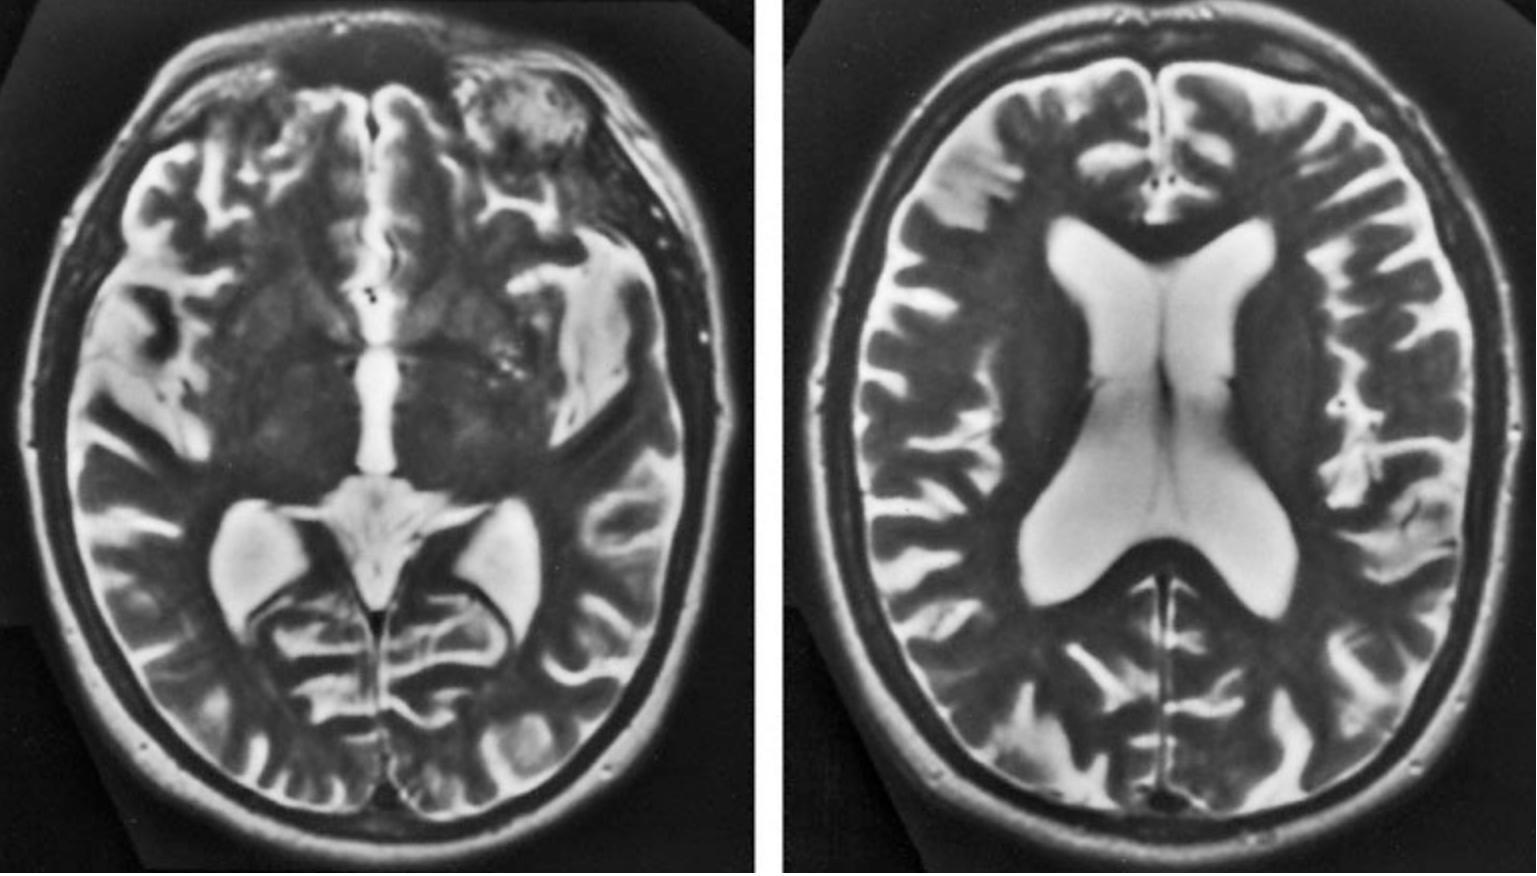

A 73-year-old woman is brought to the clinic by her husband because of a 6-month history of progressive memory difficulty. During this time, she has misplaced objects more frequently than usual and has had trouble following recipes. Six days ago, she became lost while walking their dog in their neighborhood. Today, she forgot that their daughter had called the previous day. The patient has type 2 diabetes mellitus and hypertension. Her medications are metformin and lisinopril. She does not smoke cigarettes or drink alcohol. Vital signs are within normal limits. Physical examination shows no abnormalities. On mental status examination, she is oriented to person but not to place or time. She recalls zero of three objects after 5 minutes. She makes four errors when performing serial sevens. She can name the US President and Vice President. She can name eight animals in 1 minute. The remainder of the examination shows no abnormalities. Results of a complete blood count, her erythrocyte sedimentation rate, and results of liver and thyroid function tests are within the reference ranges. VDRL testing for syphilis is negative. MRIs of the brain are shown. Which of the following is the most appropriate next step in management?